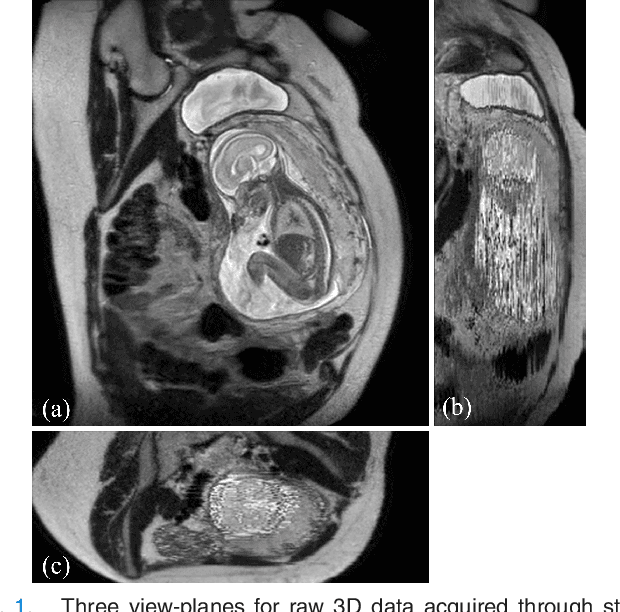

Abstract:In this paper we present a novel method for the correction of motion artifacts that are present in fetal Magnetic Resonance Imaging (MRI) scans of the whole uterus. Contrary to current slice-to-volume registration (SVR) methods, requiring an inflexible anatomical enclosure of a single investigated organ, the proposed patch-to-volume reconstruction (PVR) approach is able to reconstruct a large field of view of non-rigidly deforming structures. It relaxes rigid motion assumptions by introducing a specific amount of redundant information that is exploited with parallelized patch-wise optimization, super-resolution, and automatic outlier rejection. We further describe and provide an efficient parallel implementation of PVR allowing its execution within reasonable time on commercially available graphics processing units (GPU), enabling its use in the clinical practice. We evaluate PVR's computational overhead compared to standard methods and observe improved reconstruction accuracy in presence of affine motion artifacts of approximately 30% compared to conventional SVR in synthetic experiments. Furthermore, we have evaluated our method qualitatively and quantitatively on real fetal MRI data subject to maternal breathing and sudden fetal movements. We evaluate peak-signal-to-noise ratio (PSNR), structural similarity index (SSIM), and cross correlation (CC) with respect to the originally acquired data and provide a method for visual inspection of reconstruction uncertainty. With these experiments we demonstrate successful application of PVR motion compensation to the whole uterus, the human fetus, and the human placenta.